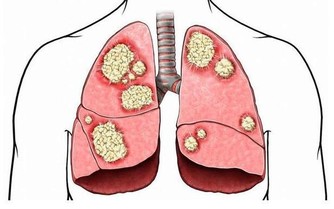

所謂內源性尿酸,是人體代謝過程中自行產生的。當體內嘌呤代謝紊亂,或惡性腫瘤等疾病患者因放化療使腫瘤細胞大量破壞分解,也會導致血尿酸水平的急劇上升。